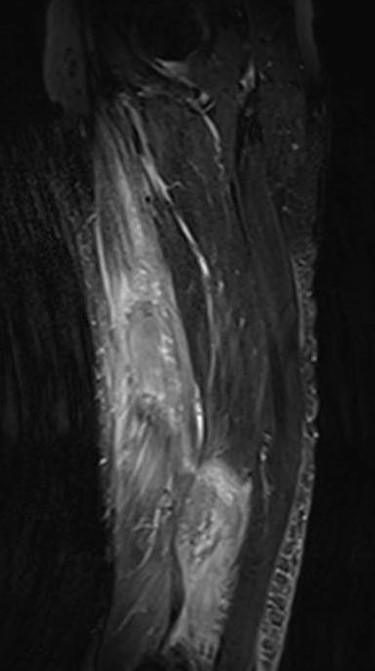

The clinical case consisted of a 79-year-old male patient with a medical history of atrial fibrillation and pulmonary embolism diagnosed 2 years ago. Among the prescribed medications, rivaroxaban was given as an anticoagulant therapy. The patient was lying in bed when a sudden onset of a sprain-like pain appeared on his right thigh region. He had difficulty walking and observed the progression of a large ecchymosis along the thigh, extending from the greater trochanter of the femur to above the patella. Later as the clinical manifestations worsened, the patient arrived at the emergency department. At the hospital, the treating physician noticed edema, ecchymosis and pain confined to the thigh region; therefore, ordered laboratory studies, such as prothrombin time, international normalized ratio and hemoglobin were all within the normal range for the patient’s age and comorbidities. The doctor solicited a magnetic resonance imaging (MRI) study to evaluate the thigh region where a rupture and hematoma regarding the sartorius muscle was evident. The MRI displayed a hyperintense area representing blood collection and discontinuity in the trajectory of the sartorius muscle (Figs 1–3). The hematoma was large in volume, hence surgical drainage was performed. After the procedure, the patient’s pain diminished considerably and was ordered to rest. Posteriorly, the patient began rehabilitation exercises and cooperated with follow-up dates to test progression. The patient attended a follow-up appointment after 6 months of initial presentation where a positive clinical outcome and enhanced walking capacity was observed.

MRI coronal view displaying hematoma and rupture of sartorius muscle.